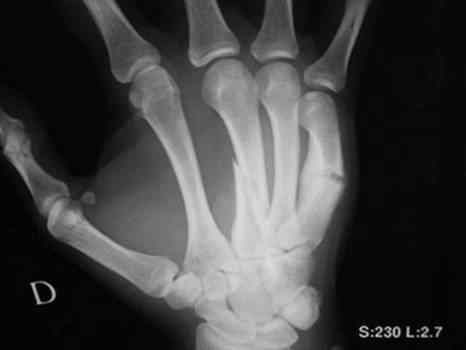

Косой перелом 3 пястной и повторный перелом 5 пястной кости на фоне старой мозоли

- со слов предыдущая травма около месяца назад. Какова тактика лечения ?

так вроде бы на 3-й укорочение небольшое есть, если не скрыпач, может и сойдет. Я бы лично дистракцию интраоперационно и закрыто спицами сделал. 5-ю можно и не трогать. если конечно не возиться с корригирующими остеотомиями и .т.п. Видать пациент, любитель подраться, больно уж перелом типичный на 5-й. Можно и гипс конечно на 4 недели. Все зависит от запросов пациента. Сделайте снимок здоровой, а лучше обе кисти на одну кассету рядом и измерьте длину 3-х костей. Все станет ясно, думаю.

Ув. Владимир. данный вид перелома 3-й относится к варианту нестабильного перелома, хотя и смещение пока не столь значительное я бы зафиксировал данный перелом спицами, но можно и пластиной, винтами и т.д. по отношению к 5-й если больной настаивает можно сделать корегирующую остеотомию и фиксацию, но дело не благодарное. если психический статус больного непозволяет жить без травм кисти - гипсовая повязка и флаг в здоровую ,пока, руку.

Проблема таких переломов в посттравматической контрактуре, которая развивается часто при длительной иммобилизации и плохой разработке. Если провести стабильный остеосинтез и оставить больного без гипса, то почему бы и нет? Но практика показывает, что и консервативный подход неплох в этом случае, если не увлекаться длительной иммобилизацией.

Планируется выполнить остеосинтез III и V пястной кости мини-аппаратом РНЦ "ВТО", срок фиксации 1 - 1,5 месяца.Гарантируется полное восстановление размеров и формы пястных костей, при соответствующем ЛФК - функции.